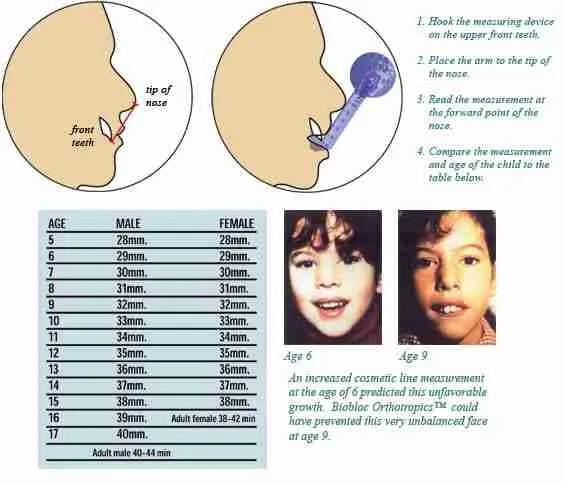

This kinda reminds me of the mew indicator line, indicator cheek line and what'd he go about evaluating SN line, FN plane and Cranial base angles

This kinda reminds me of the mew indicator line, indicator cheek line and what'd he go about evaluating SN line, FN plane and Cranial base angles

View attachment 4063432View attachment 4063433View attachment 4063434View attachment 4063436View attachment 4063438View attachment 4063439View attachment 4063440